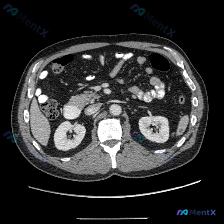

整理了一个很有警示意义的影像读片场景,特别能体现「循证影像诊断」的重要性。 先看「预设问题」与「影像事实」的冲突 预设: 临床/提问指向「图中存在脾脏病变」 影像事实(单帧增强CT): - 扫描层面:仅上腹部,显示肝右叶部分、胆囊、双肾、胰腺、血管、胃及肠管 - 强化状态:增强扫描(血管强化明显),...

整理了一份挺有意思的影像分析资料,和大家聊聊思路。 病例/影像背景 临床预设存在“脾脏病变”,提供了一张腹部CT横断面(软组织窗)图像。 影像核心观察 我先把图像里的关键信息理一理: 1. 脾脏本身:左侧脾脏形态、大小、实质密度都大致正常,没有看到局灶性的低密度或高密度影,边缘也光滑 2. 其他腹部...